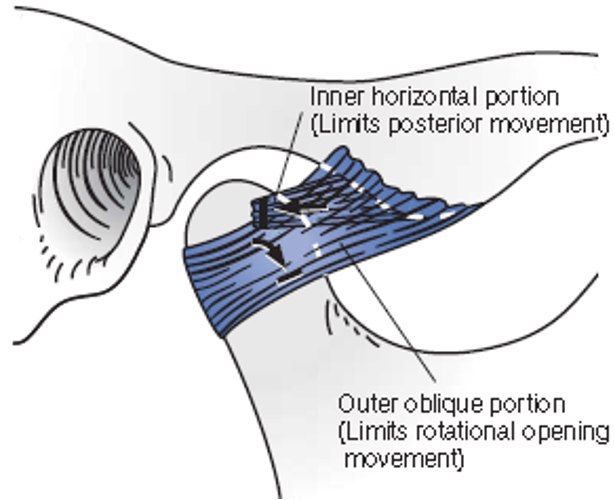

Ligament

- Temporomandibular ligaments

- Inner horizontal protion

限制向後 - Outer horizontal protion

限制旋轉、平移

- Inner horizontal protion